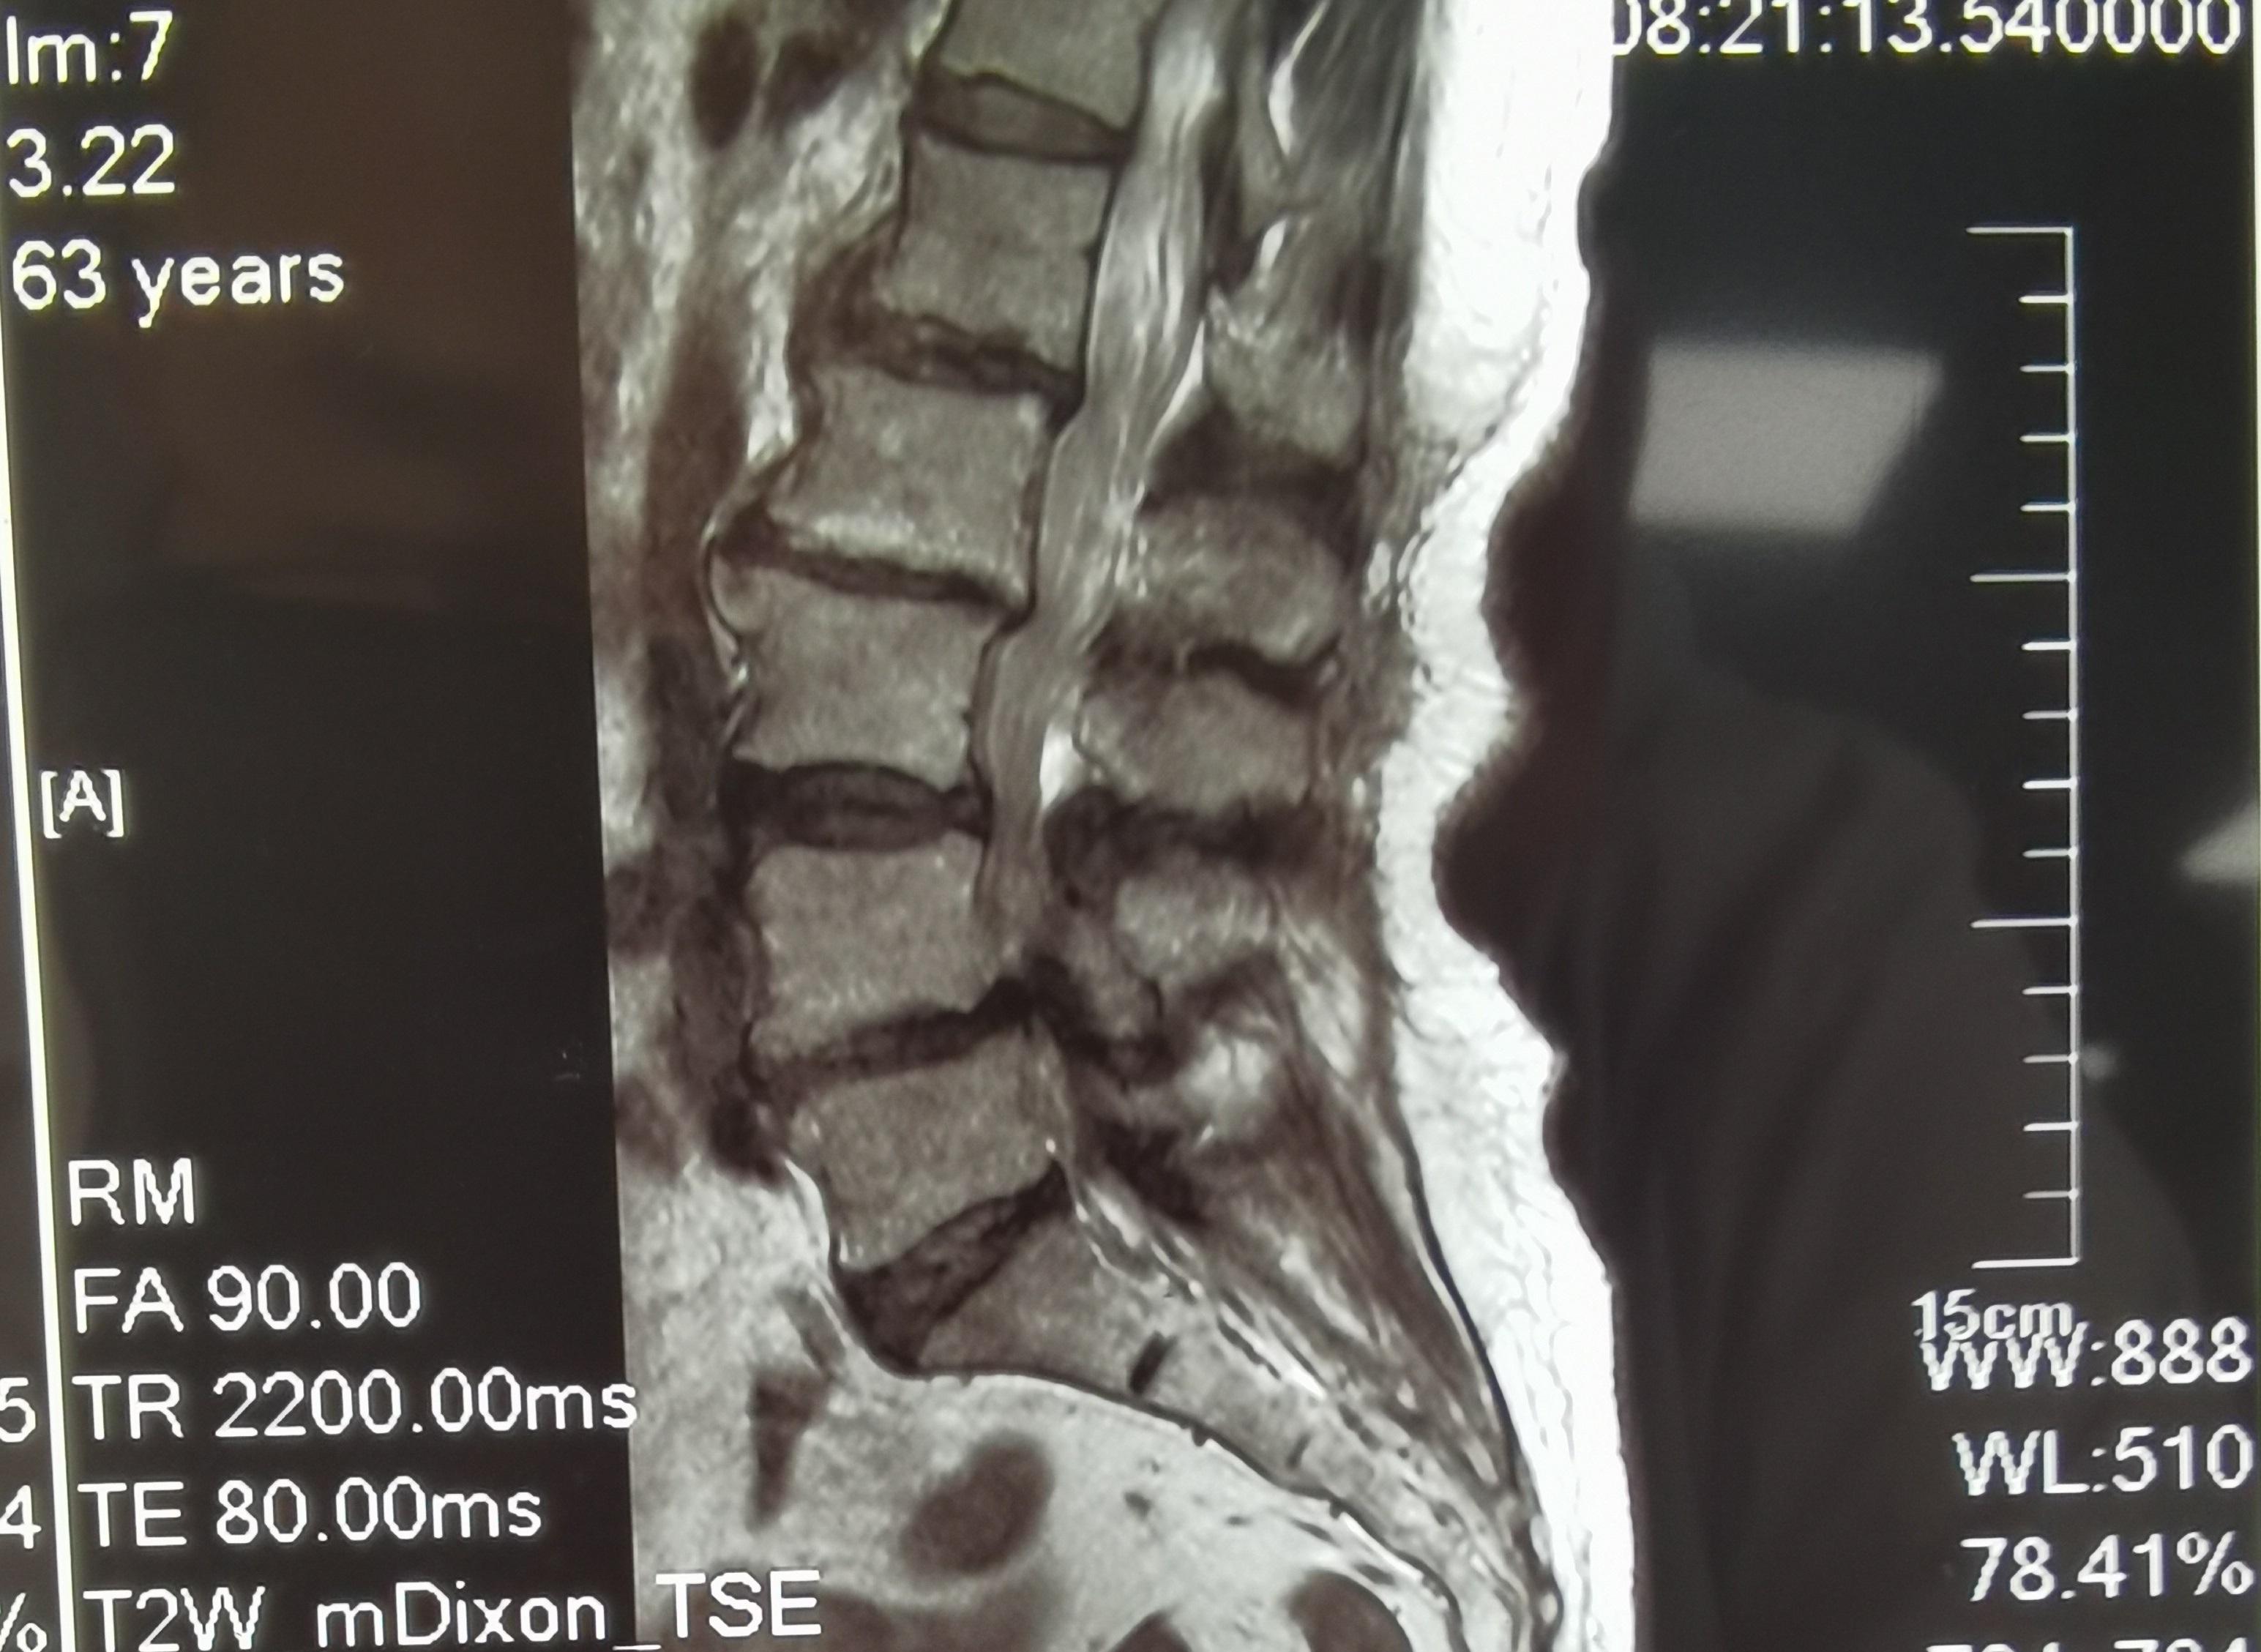

经详细问诊,检查结果显示: 患者腰椎生理性前凸消失,腰椎活动略受限,L4椎体一度前滑脱,腰椎管狭窄,腰椎退行性改变。